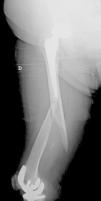

All of the patients walked with the aid of orthopaedic devices prior to the fracture, 3 with a walking frame and 4 with crutches. Union took place in all cases with a mean of 4.5 months,4–7 two of them had diaphyseal fractures with delayed union. There were no angles in union greater than 5°, no reoperations or complications or evolutionary complications presented, even in one patient with a short plate which only overlapped 3cm who made satisfactory progress (Fig. 2). All the patients regained their walking ability prior to the fracture except for one female patient who was lost to follow-up at 6 months, the fracture having healed. Clinically, the three patients with a supracondylar fracture lost a mean of 20° knee flexion, previous hip mobility was not altered in any of the patients.

We have followed the abovementioned criteria, using a single lateral angular-stable plate in all cases covering the entire interprosthetic femoral segment, achieving union in all cases with no reoperations or failures. The only problem that we found was achieving an adequate overlap of the osteosynthesis plate to the femoral hip implant, since the reduced availability of plate lengths means that occasionally we have to make a rather limited or excessive overlap; a choice has to be made between one or the other.